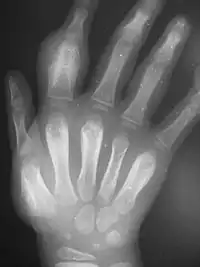

An irregularly-thickened first finger; proximal fingerbone is asymmetrically swollen

Dactylitis of secondary yaws due to periostitis

radiograph showing same hand with thickened bones

Periostitis of secondary yaws may be visible on an x-ray, even if not otherwise visible[2]